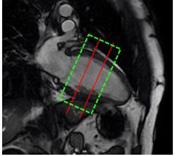

Planification des séquences

La séquence d’OS a été établie, et on peut voir ce qui se passe au cours des différentes phases des manœuvres respiratoires. L’étape suivante consiste à planifier cette séquence, ce qui est très simple. La première coupe est une coupe mi-basale qui est stratégiquement placée pour éviter la voie d’éjection du ventricule gauche (LVOT), et les valves atrio-ventriculaires. La deuxième est une coupe mi-ventriculaire. On vérifie le cycle cardiaque pour s’assurer du bon positionnement. Notez 3T GE

comment le shim est concentré autour des deux coupes et non du cœur complet ! (figure 2.)

Figure 2 : Images montrant les positions correctes des coupes mi-basale et mi-ventriculaire et le bon placement du shim. A- Aspect 4 chambres, B- Aspect 2 chambres et C- Coupe axiale.